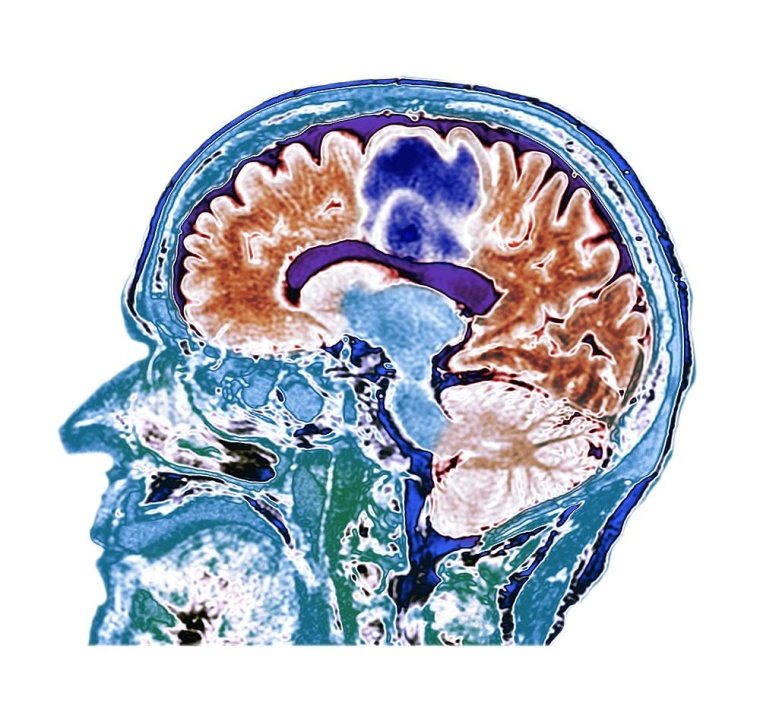

Spezielle Versorgung für Kinder und Jugendliche mit Gehirnerschütterung

Fast 115.000 stationäre Krankenhausaufenthalte von Kindern und Jugendlichen waren im Jahr 2019 in Deutschland auf eine Kopfverletzung zurückzuführen, meist eine Gehirnerschütterung – auch als Concussion oder leichtes Schädelhirntrauma (SHT) bezeichnet.

In der Concussion Clinic am Dr. von Haunerschen Kinderspital (Pädiatrie & Kinderchirurgie) bietet das LMU Klinikum eine spezielle Versorgung für Kinder und Jugendliche mit Gehirnerschütterung an.